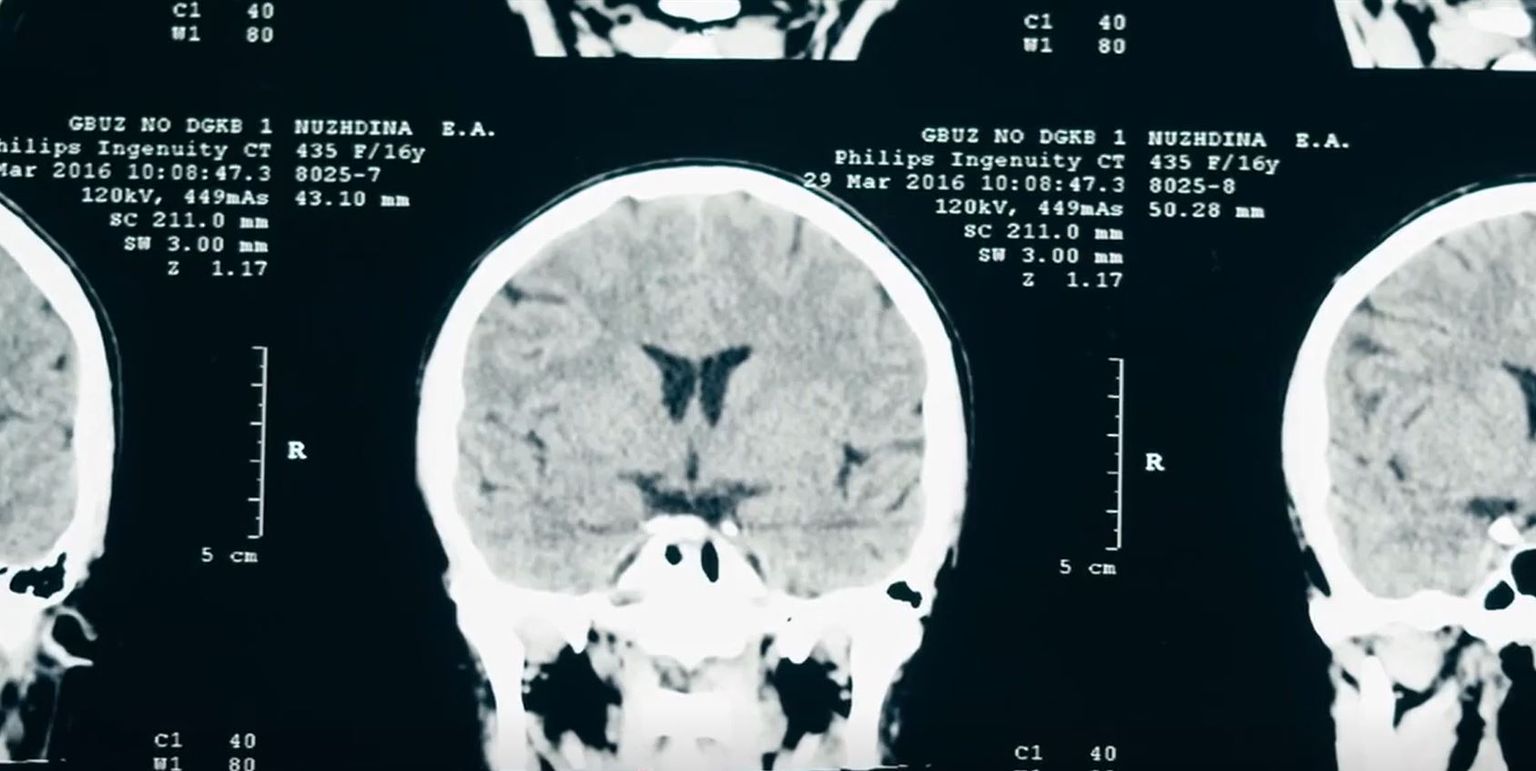

Otkriće našeg mladog znanstvenika o kojem pišu svjetski mediji: "Lakše je pomoći teško oboljelima kad imate alat"

• Uspjeh hrvatskog znanstvenika u istraživanju halucinacija - 3 Foto: DNEVNIK.hr